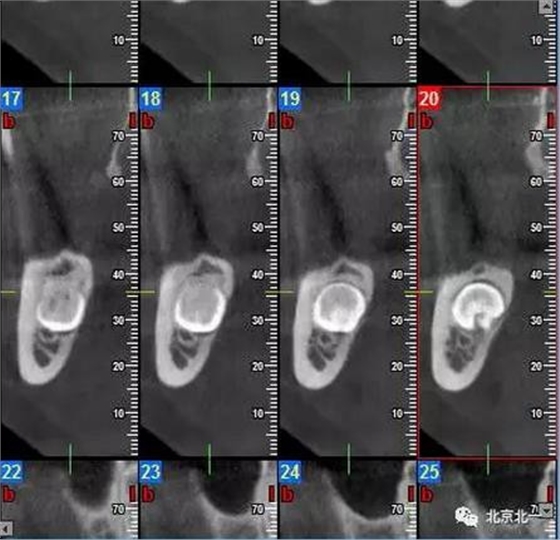

圖一:CBCT顯示右側(cè)下頜水平骨埋伏牙,牙冠距離下牙槽神經(jīng)管接近。

圖三:截面圖顯示神經(jīng)管位置。